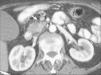

Varias cadenas ganglionares drenan el páncreas. La cabeza de la glándula drena hacia la cadena del surco pancreaticoduodenal y a través de ella, en los grupos ganglionares subpilórico, portal, mesocólico, mesentérico y aortocaval. El cuerpo y cola pancreáticos drenan hacia los grupos ganglionares retroperitoneales, hacia el hilio esplénico, o bien hacia los ganglios de la cadena celíaca, aortocaval, mesocólica o mesentérica. La mayoría de estudios valoran como metastáticas las adenopatías que miden más de 1 cm en su eje corto, no obstante ganglios de tamaño normal pueden contener micrometástasis, mientras que ganglios aumentados de tamaño pueden ser reactivos (fig. 9). Esto supone una importante limitación para la TC que evalúa únicamente en función de parámetros anatómicos. No obstante, como los ganglios regionales a menudo pueden ser resecados en la cirugía no representan una contraindicación quirúrgica formal.

Fig. 9.--Tomografía computarizada en fase pancreatográfica en un paciente con neoplasia de cabeza pancreática que muestra adenopatías de 15 mm de diámetro máximo en región celíaca (puntas de flechas) que resultaron ser reactivas en el estudio anatomopatológico.

Algunos autores han evaluado el rendimiento de la TC en la detección de invasión ganglionar por adenocarcinoma de páncreas14,17,19,32,44, obteniendo valores de precisión diagnóstica de la TC helicoidal bifásica que oscila entre el 58% y el 78,3% para la infiltración tumoral ganglionar. En conclusión, la TC tiene todavía una tendencia hacia la infravaloración de la invasión metastásica ganglionar en parte debida a una alta frecuencia de linfadenopatías reactivas concurrentes. Dado que los ganglios peripancreáticos pueden ser resecados en bloque junto con el tumor primario, la identificación de adenopatías peripancreáticas de tamaño superior a 1 cm en pacientes con tumores por lo demás considerados resecables, no debe contraindicar la cirugía dado el bajo rendimiento de la TC en el diagnóstico de la invasión ganglionar.